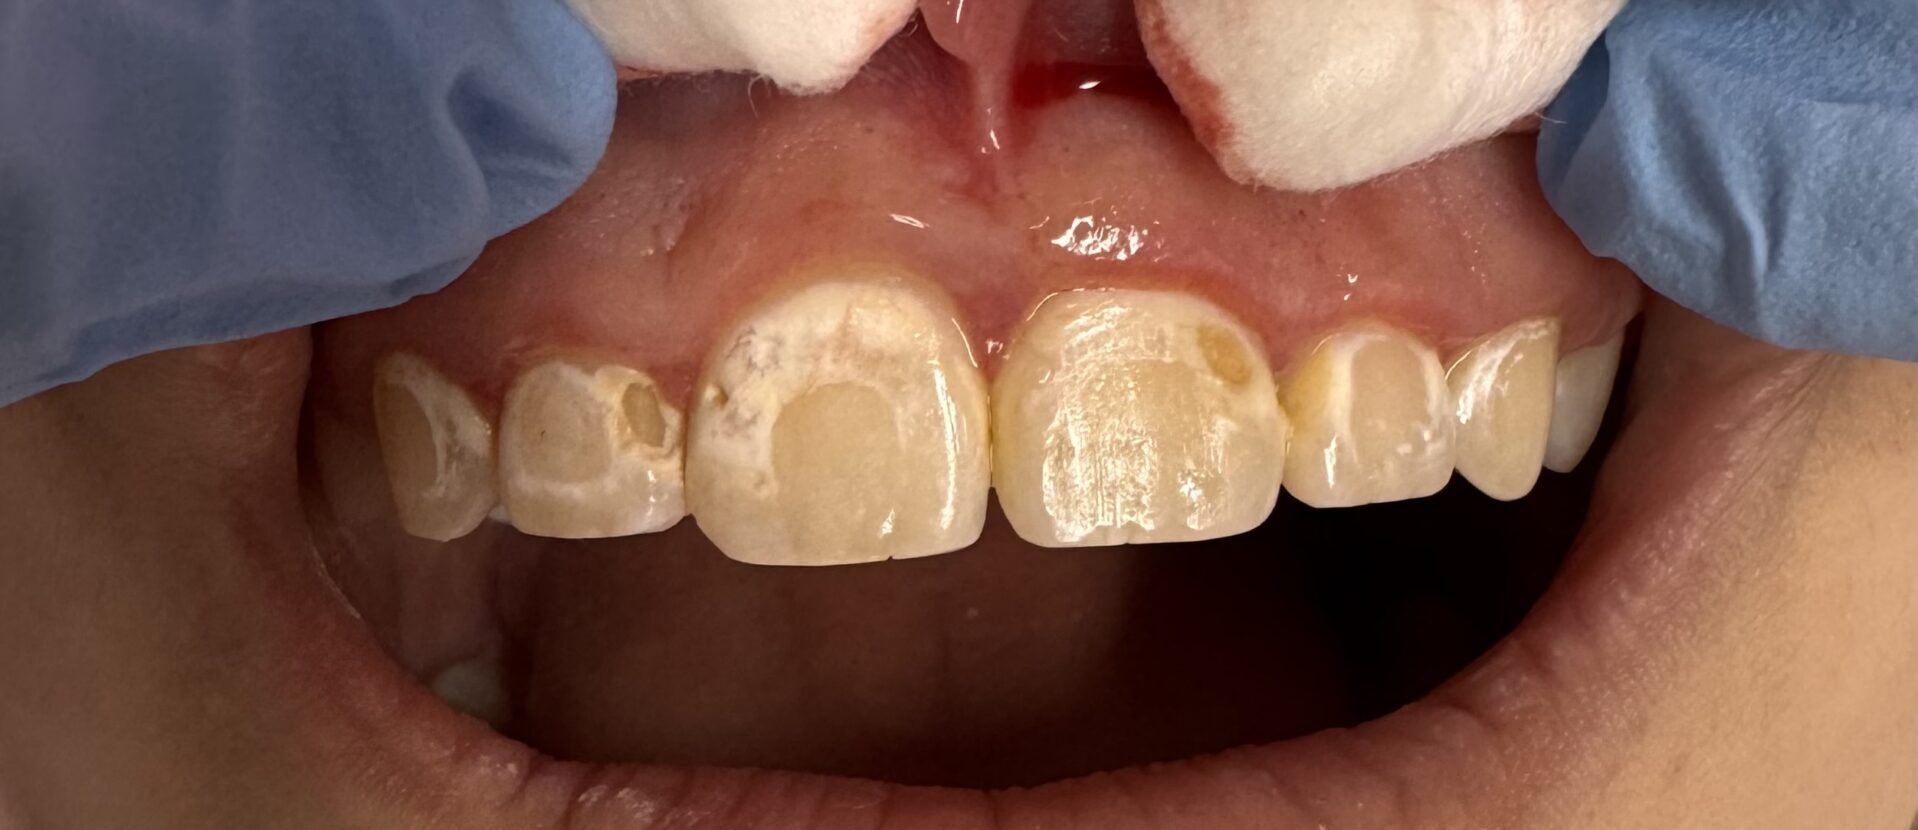

A teenage patient came to see Dr. Pashmini soon after she had her braces removed, and cavities were present on all her front teeth, where the brackets used to be.

This patient presented with a significant and deeply concerning issue: issues were caused by braces and multiple cavities caused by not brushing/flossing thoroughly during the treatment. This wasn’t merely a cosmetic concern; the patient had been living with this condition for an extended period, leading to considerable discomfort, multiple cavities and a decline in their overall quality of life. The impact extended beyond physical symptoms, affecting their confidence and daily interactions.